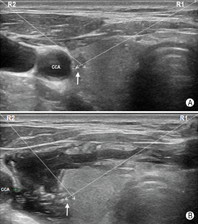

如图19所示,对于气管近旁尤其是2~5点钟位(以甲状腺横切面为参照表盘,于对侧腺体则应是7~10点钟位)的目标结节,穿刺操作宜选用由内向外穿刺法,同时操作者可使用液体隔离技术使目标病灶向外侧移位,增大端侧式穿刺进针的角度,以规避气管壁对穿刺针尖的阻碍,并改善穿刺针尖的显示清晰度。如图20所示,对于位于7~10点位(对侧腺体应是2~5点位)邻近颈总动脉的病灶,也宜选用由"内向外"穿刺法。同样,操作者也可采用液体隔离方法使得颈总动脉向外侧移位,增大目标病灶与颈总动脉之间的距离,避免误伤颈总动脉。

专家意见:液体隔离法技术可促使甲状腺结节或甲状腺周围毗邻结构移位,优化穿刺路径,营造安全操作空间。